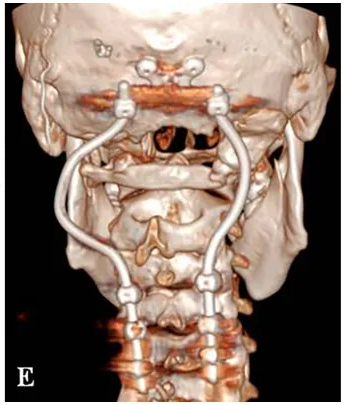

事实是,为了尽可能安全地切除肿瘤,福教授为其制定了一个综合治疗方案,而教授在术中所使用的,除了“筷子技术”,还有“双镜联合”技术。首先在显微镜下暴露肿瘤并进行瘤内减压,再使用神经内镜辅助探查,并借助“筷子技术”切除对侧肿瘤。最后,福教授还使用Roy-Camille技术进行枕颈融合术,为后续质子治疗创造一个无金属的定位及治疗通道。

术后三维CT显示C0-C3-C4-C5枕颈融合稳定,根钉的弯曲设计有助于PBRT放疗的实施。